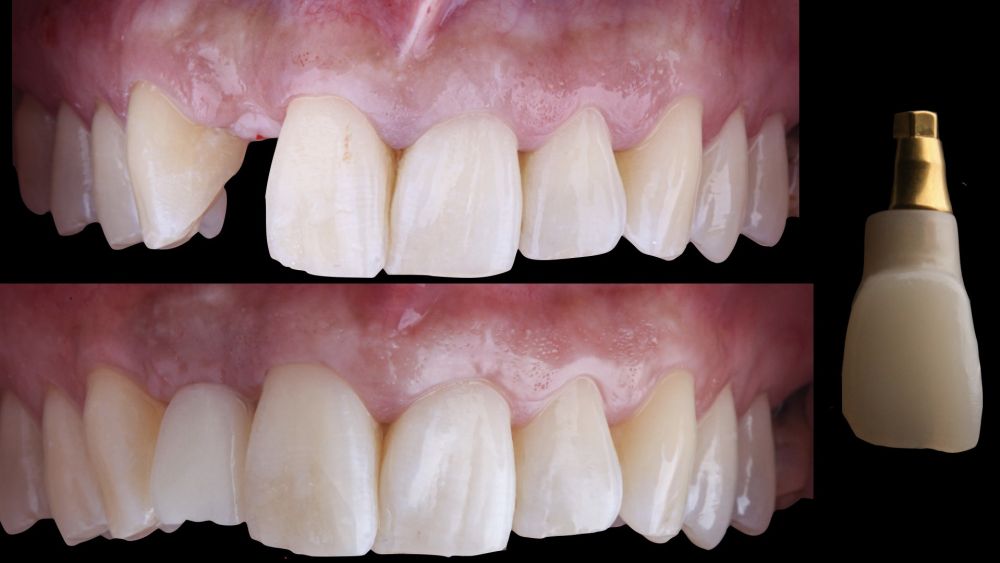

-Fase II: la cicatrización transcurrió sin complicaciones. Tras 5 meses de la cirugía de preservación alveolar, se planificó la cirugía implantológica guiada en posición 1.2 (Figura 2). Para ello, se utilizaron un archivo DICOM procedente de la tomografía computarizada de haz cónico (CBCT) y el archivo STL procedente del escaneado mediante un escáner óptico intraoral. Con esta información se construyó una férula quirúrgica de soporte dental (Figura 3). La férula quirúrgica se ancló sobre los dientes y guió la realización del lecho implantario y la colocación del implante. La técnica quirúrgica de cirugía guiada consistió en una cirugía con colgajo, preparando e insertando el implante (3,5 x 11,5 mm) según el protocolo estandarizado de cirugía guiada Nobel Active® (Nobel Biocare AB, Gothenburg, Sweden). Una vez colocado el implante 1.2, se obtuvo un injerto gingival compuesto de epitelio y tejido conectivo de la mucosa masticatoria palatina. A continuación, se realizó la desepitelización de la capa superficial de dicho injerto fuera de boca mediante una hoja de bisturí 15C con la finalidad de obtener un injerto de tejido conectivo de la capa subyacente18.

El injerto desepitelizado se insertó y posicionó por vestibular y oclusal mediante un punto colchonero horizontales utilizando sutura 5-0 no reabsorbible (Figura 4)19.

-Fase III: tres meses tras la colocación del implante, la situación del tejido blando era favorable (Figuras 5 y 6). Se tomó una impresión digital mediante escáner intraoral para la realización de un provisional atornillado de polimetilmetacrilato (PMMA). Respecto a la corona implantaria definitiva se realizó una restauración cemento-atornillada con una interfase de titanio nitrurado adaptando el diseño al perfil de emergencia ya consolidado con la prótesis provisional. La corona se realizó por CAD-CAM en zirconio con reducción completa y estratificación de cerámica feldespática de recubrimiento para zirconio (Figura 7).